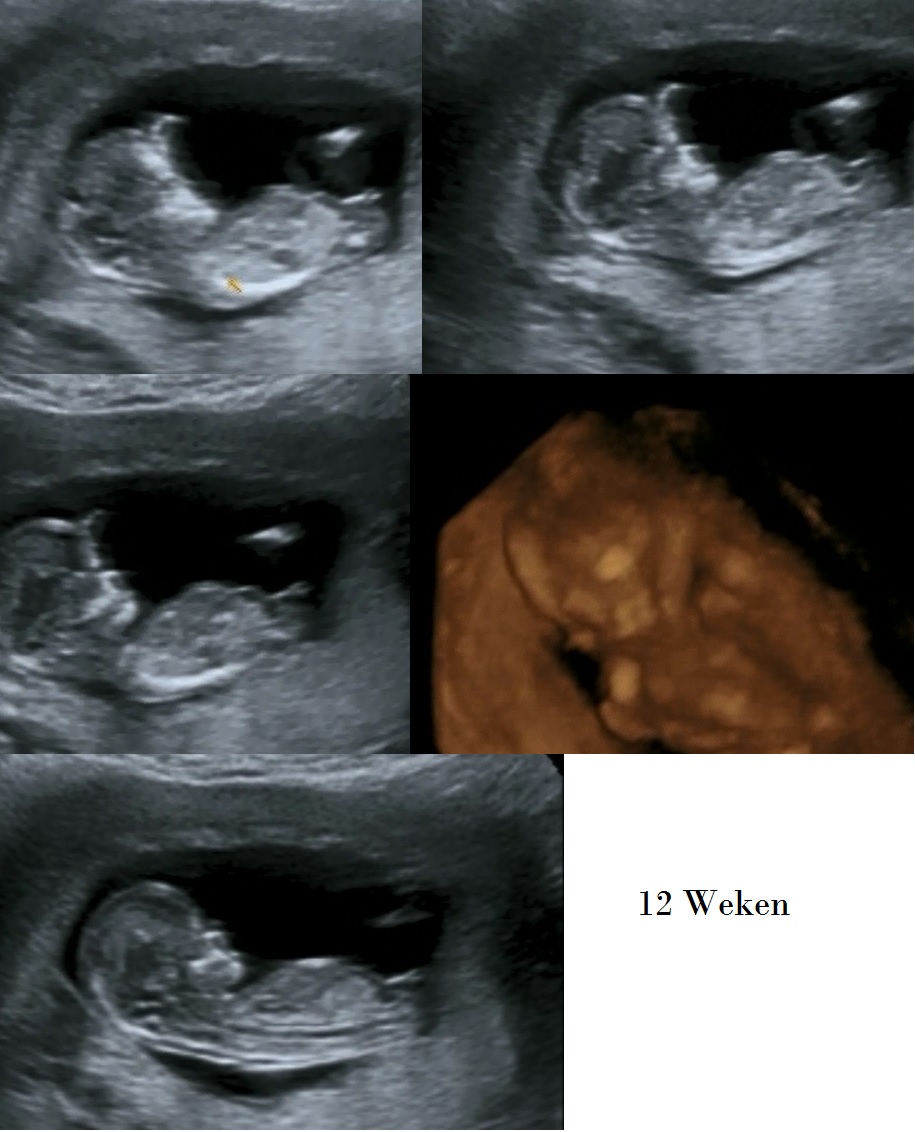

The Echo is taken by 11+6 weeks, im today 12 weeks.

girl

Girl except 2nd from the bottom looks boyish.

I feel it's too early to guess. If pushed I'd lean girl but it may still have time to rise so it's a very cautious girl lean from me. GL! Hope it's whichever gender you wish for :)

It's too early and seems to angle up slightly even this early which would make me lean boy but it also very long which makes me leans girl...so idk!!!

I'm guessing boy

Boy